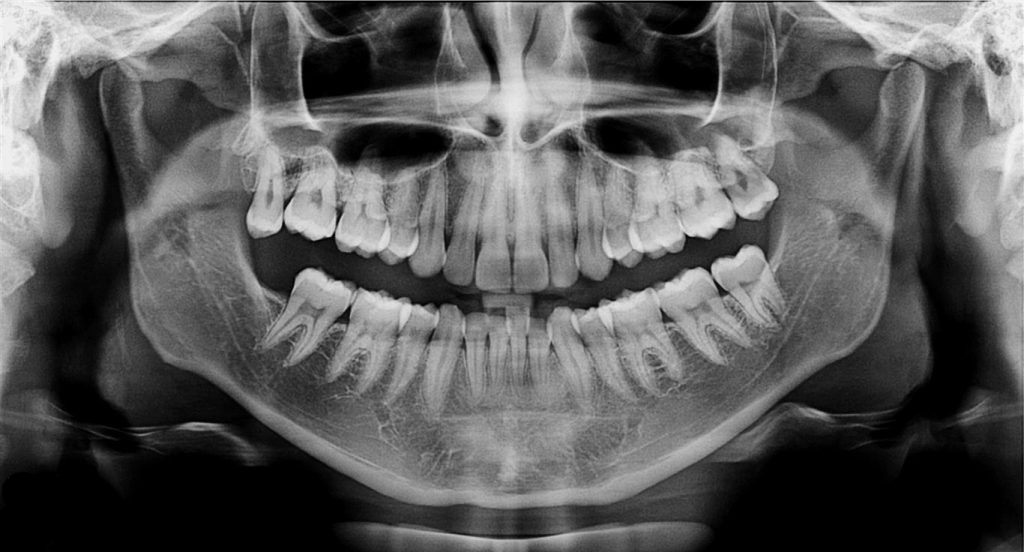

Ofrecemos la más alta tecnología con una atención profesional y personalizada por parte del equipo altamente calificado en donde contará con el mejor estudio para sus pacientes.